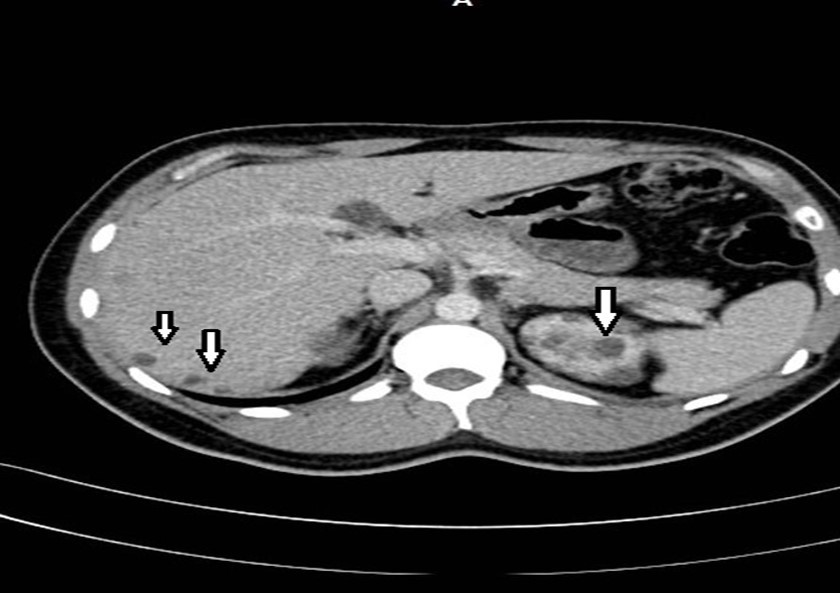

Abdominal tomography reported hepatomegaly secondary to polycystic disease and was reported with 3 cysts of greater size of 17, 14 and 12 cm in approximate diameter (Figure 1, Figure 2), kidney transplant without problems; the liver with mass effect on the stomach, the vena cava partially occluded, uncomplicated colon diverticulosis. Laboratory creatinine 1.44mg/dl urea 51.9 md/dl, glucose 71mg/dl, normal liver function tests.

Figure 2.Non-contrast CT shows multiple liver cysts with variable size and multiple renal cysts.